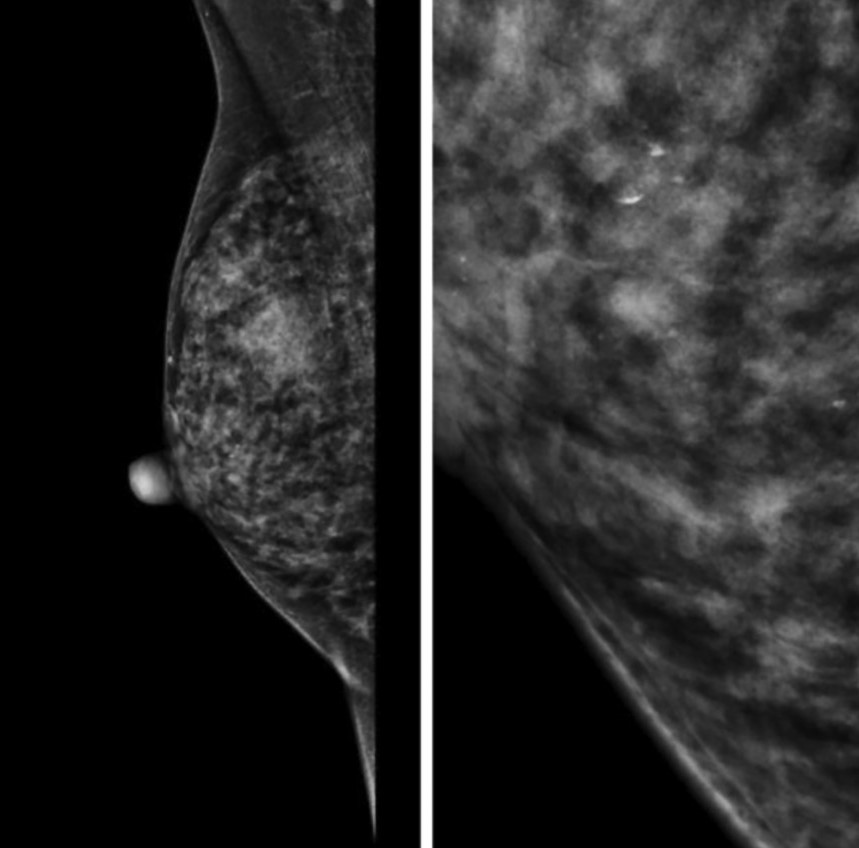

Для фиброзно-кистозных изменений характерны кальцинаты по типу Weddell. Как правило, они имеют квадратную, треугольную или трапецивидную форму (Рис.4).

Округлые кальцинаты с просветлением в центре, кальцинаты по типу «яичной скорлупы» характерны для обызвествления макро- и микрокист (Рис.5).